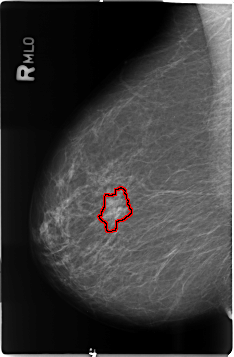

B_3506_1.RIGHT_MLO

RIGHT_MLO LINES 4632 PIXELS_PER_LINE 3032 BITS_PER_PIXEL 12 RESOLUTION 50 OVERLAY

FILE: B_3506_1.RIGHT_MLO.OVERLAY

TOTAL_ABNORMALITIES 1

ABNORMALITY 1

LESION_TYPE MASS SHAPE FOCAL_ASYMMETRIC_DENSITY MARGINS ILL_DEFINED

ASSESSMENT 4

SUBTLETY 3

PATHOLOGY MALIGNANT

TOTAL_OUTLINES 1

BOUNDARY